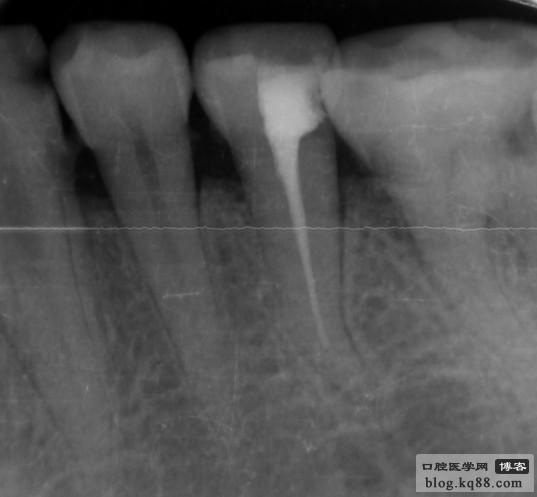

左下5側(cè)支根管被根充